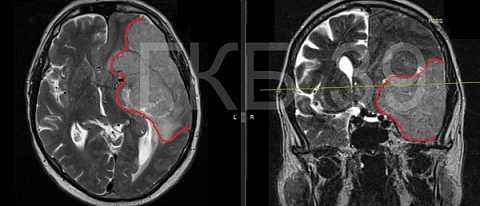

Согласно информации, в марте текущего года в больницу обратился 66-летний мужчина. В ходе обследования врачи диагностировали у него опухоль головного мозга, размер которой составлял 10х7х6,5 см. Она занимала почти треть левого полушария. Существовала угроза жизни пациента.

Мужчину экстренно госпитализировали. Нейрохирурги приняли решение об удалении образования. Операция длилась более четырех часов. Гигантское новообразование было успешно удалено с помощью микрохирургической техники. Опухоль оказалась доброкачественной.